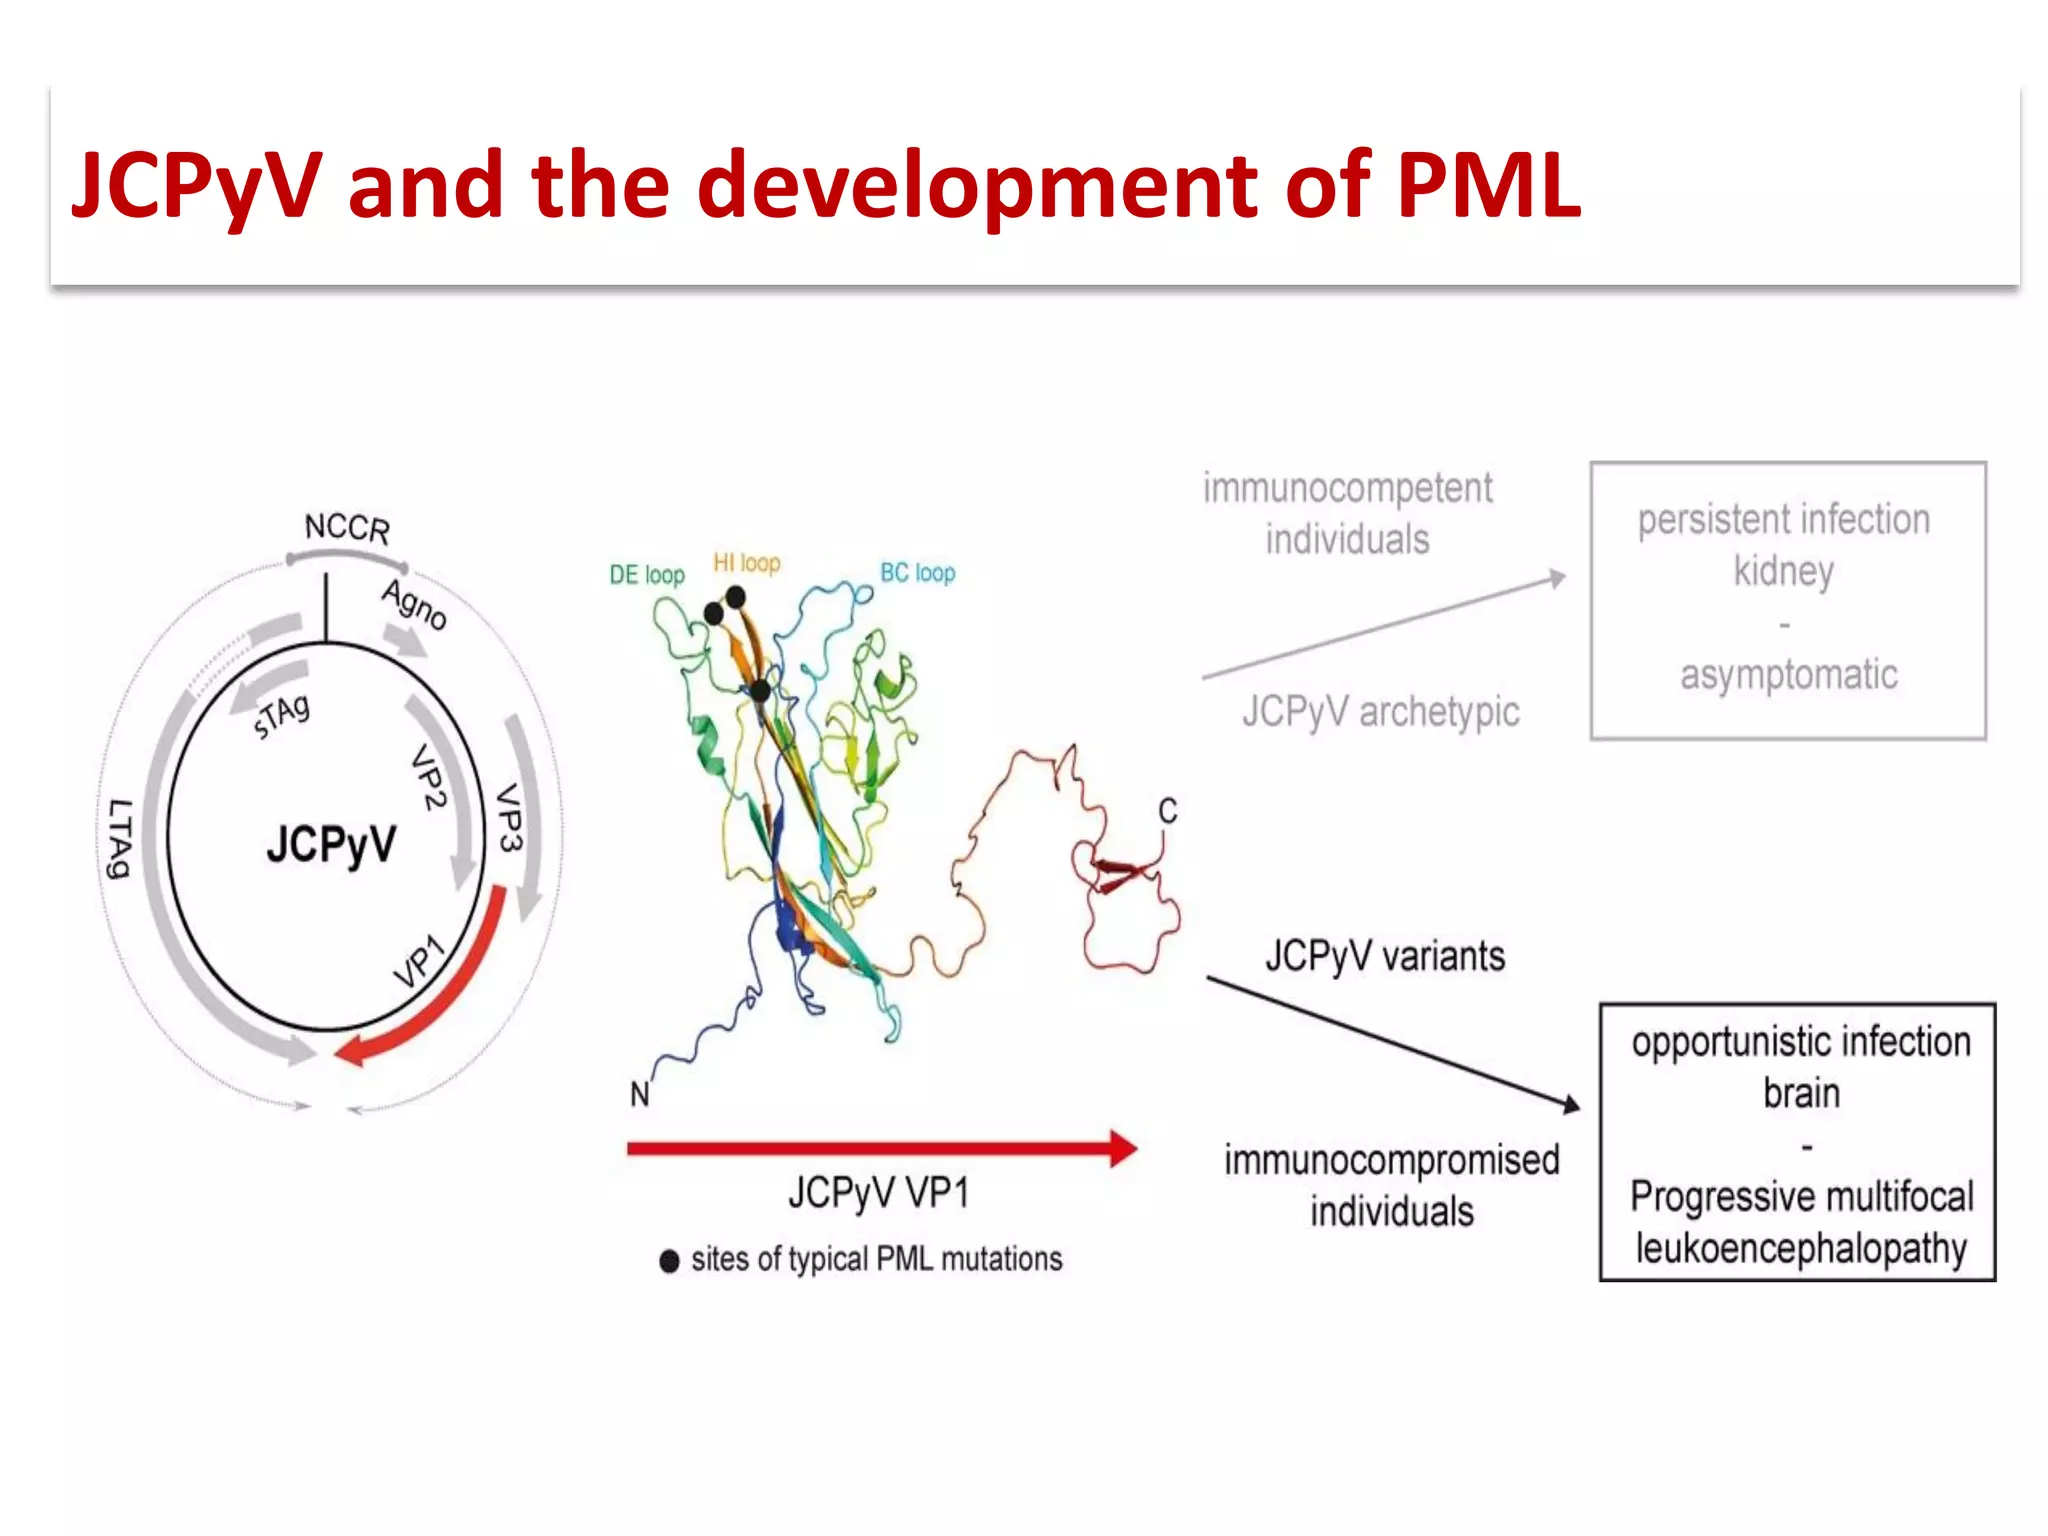

![▪ 50-90% of adults have been exposed to this virus

▪ 19-27% of these people shedding JCV in their urine.[5,7-10]

▪ Acquisition of this virus is not associated with a clinical

syndrome.[9]

▪ Opportunistic infection, caused by the polyoma virus JC virus

▪ Characterized by focal demyelination in the CNS

▪ Worldwide distribution, seroprevalence of 39-69% in adults

▪ Primary infection usually in childhood

▪ No recognized acute JC virus infection

▪ Likely asymptomatic chronic carrier state

PML: epidemiology](https://image.slidesharecdn.com/pml-220423195132/75/Progressive-multifocal-leukoencephalopathy-PML-15-2048.jpg)